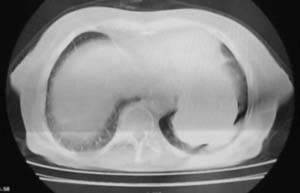

女,78岁,声嘶月余,否认有既往病史,有粉尘接触史10年。

双上肺结节融合影,周围有纤维条索影,结合粉尘接触史,首先考虑尘肺。双侧颈部有增大淋巴结,有声嘶表现,肺癌淋巴结转移不能排除。可结合颈部淋巴结活检。